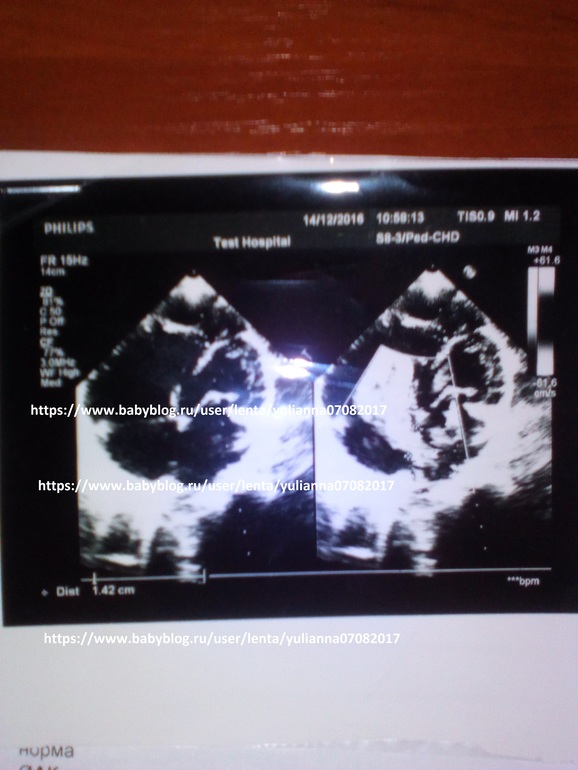

Врачи поставили страшный диагноз порок сердца дефекта межпредсердной перегородки

Срочно нужна эндоваскулярная операция с окклюдером

нужно закрытие дефекта межпредсердной перегородки окклюдером